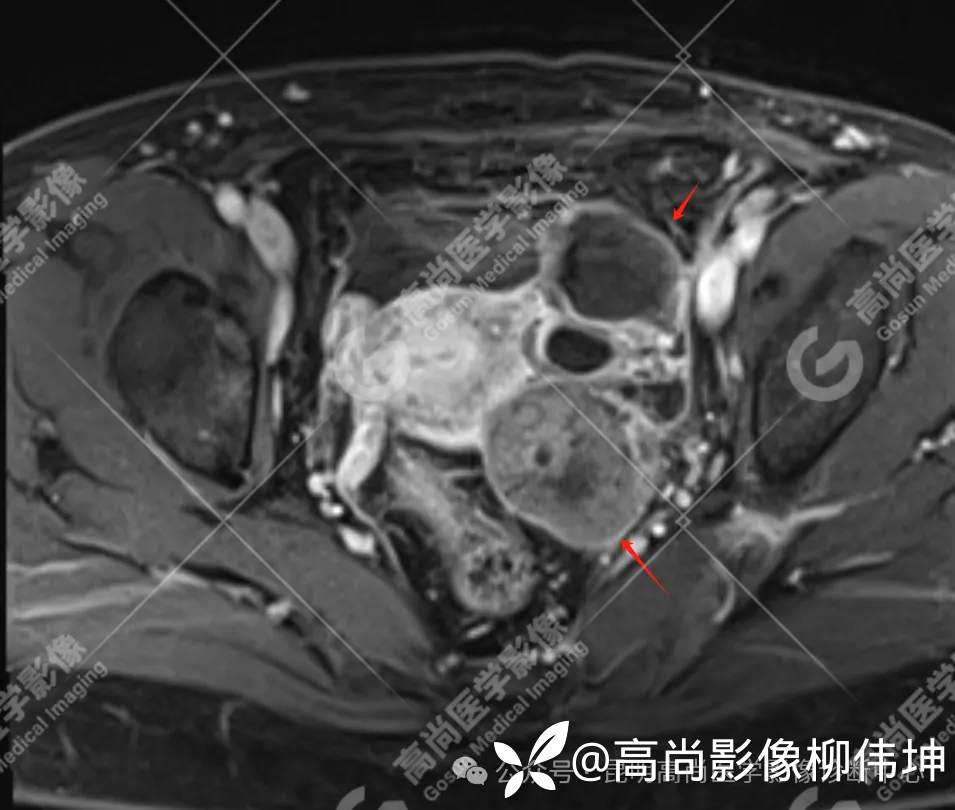

T2WI-fs-tra

(2)MRI表现:通常双侧发生,体积巨大,呈外生性、囊实性、乳头状生长,其内见大量长T1长T2液性信号影及线性分隔,囊壁厚薄不均,可见壁结节及不同比例实性成分,呈T1等信号,T2略高信号。扩散受限,DWI呈高信号,ADC呈低信号。增强扫描实性成明显强化。另外,常可检出腹水、腹膜增厚、盆壁及盆腔脏器受累、淋巴结肿大等表现。